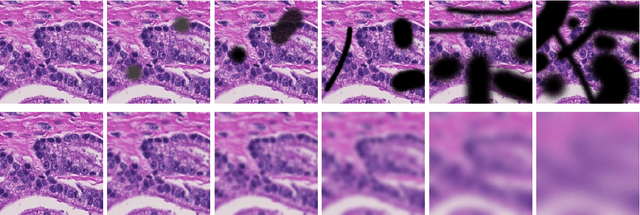

Abstract:Many deep learning methods have successfully solved complex tasks in computer vision and speech recognition applications. Nonetheless, the robustness of these models has been found to be vulnerable to perturbed inputs or adversarial examples, which are imperceptible to the human eye, but lead the model to erroneous output decisions. In this study, we adapt and introduce two geometric metrics, density and coverage, and evaluate their use in detecting adversarial samples in batches of unseen data. We empirically study these metrics using MNIST and two real-world biomedical datasets from MedMNIST, subjected to two different adversarial attacks. Our experiments show promising results for both metrics to detect adversarial examples. We believe that his work can lay the ground for further study on these metrics' use in deployed machine learning systems to monitor for possible attacks by adversarial examples or related pathologies such as dataset shift.